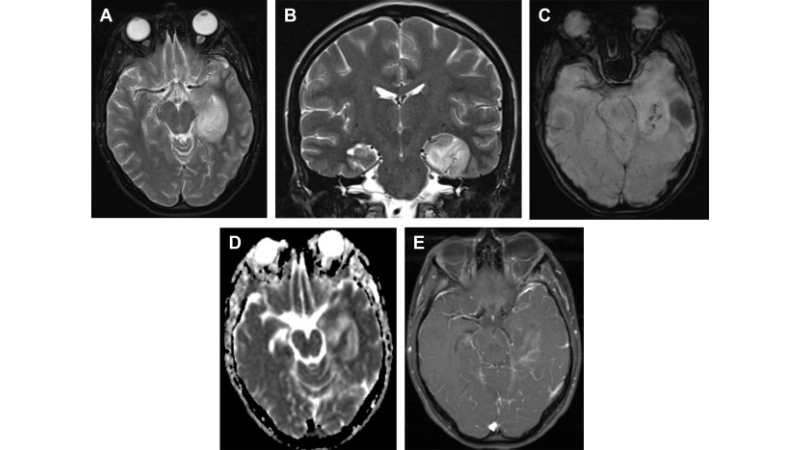

Image description of California Encephalitis

California Encephalitis is a viral infection transmitted by mosquitoes that can cause fever, headache, and neurological complications in rare severe cases. Early detection and prevention are crucial.